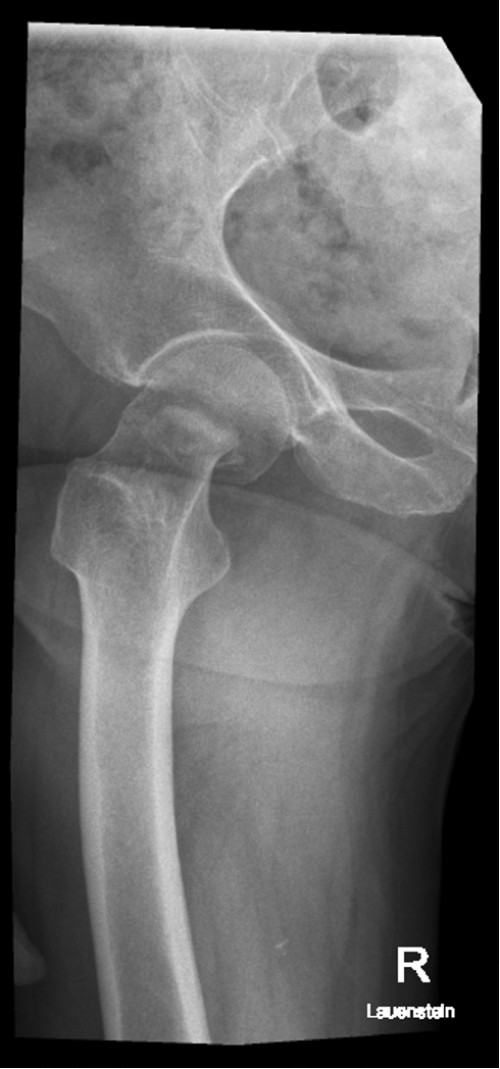

Röntgen Oberschenkel rechts Lauensteinaufnahme (axial)

Röntgen Oberschenkel rechts Lauensteinaufnahme (ax…